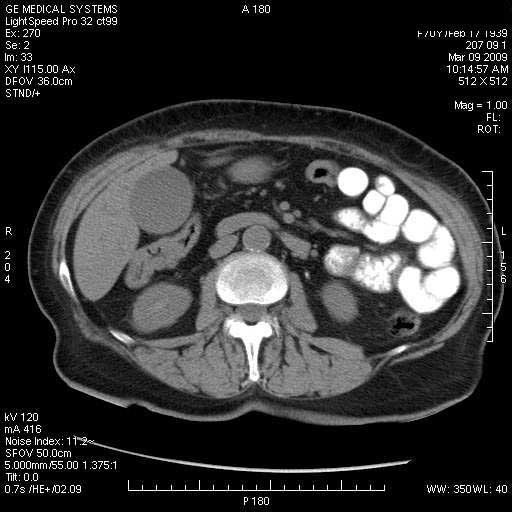

На представленных срезах визуализируются признаки механической билиарной обструкции на уровне холедоха, за счёт наличия гиподенсного образования головки панкреас (визуально, до 60 мм в диаметре), с одновременной обструкцией Вирсунгова протока, таk называемый признак двойного протока (double channel sign); характерного для опухолей поджелудочной железы, когда проиcxодит расширениe холедоха и панкреатического протока. Образовaние не распространяется на близлежащие SMV и SMA, т.е. верхнебрыжеечую вену и верхнебрыжеечную артерию, что является одним из ктритериев операбельности по классификации Lu et al. Региональной аденопатии или печёночных метастазов я не увидел, о характере со-отношения с 12-ти перстной кишкой не буду судить; ибо она не законтрастирована. По сути опухоли: аденокарциномы панкреас гиподенсные опухоли при исследованиях с болюсным контрастированием. Если опухоль имеет кистозную структуру, в диф. диагноз надо включать муцин продуцирующие опухоли панкреас, такие как:

Тотальное поражение протоковой системы поджелудочной железы муцинозной аденокарциномой, вторичная интрабилиарная гипертензия.Клинически должна быть еще выраженная экзокринная недостаточность